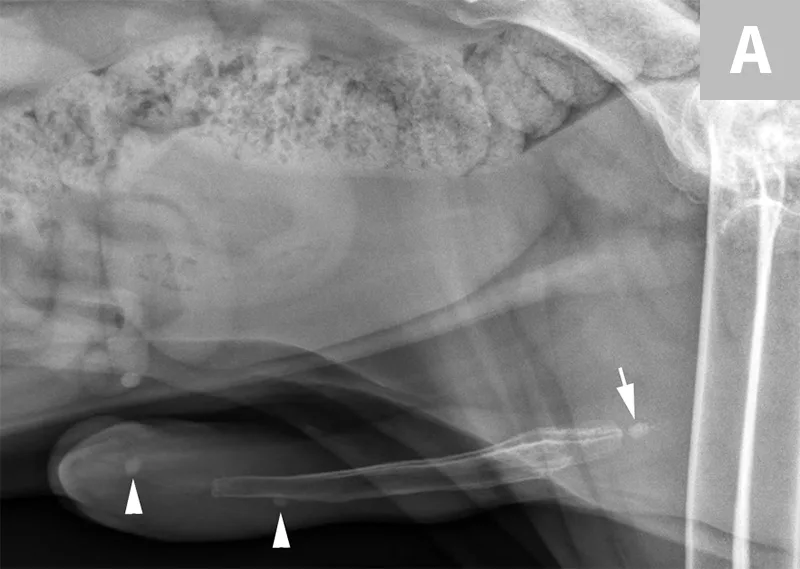

FIGURE 7A

Lateral abdominal radiograph of a cat with multiple, small, oval mineral opacities superimposed over the ventral aspect of the retroperitoneal space (arrows). These mineral opacities are arranged linearly extending from the caudal aspect of the kidneys to the level of the urinary bladder.